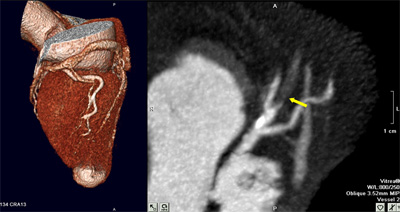

Detalle de la oclusión de la arteria descendente anterior